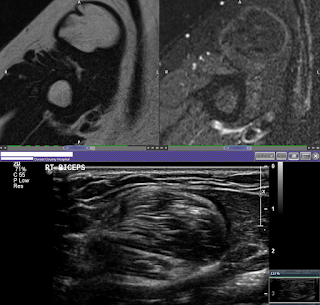

Intrabicipital lipoma Szerző: admin | aug 30, 2015 | Lump and bump, MSK, Muscular, SOL | Nincsenek hozzászólások T1w Sag & T1 FS Cor T1w Axi & T1w FS Axi & USS Sag The soft tissue mass anteriorly in the right upperarm is an approximately 4 cm intramuscular simple lipoma in biceps muscle. No features of sarcomatous change.